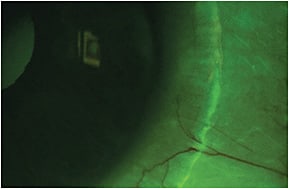

- Fluorescein Influx Fluorescein instillation in an eye fit with a spherical SL may help identify scleral toricity. When the sclera is significantly toric, the fluorescein may enter into the reservoir under the lens in a specific meridian where the lens is lifted off. The less time it takes for the fluorescein to enter into the reservoir—indicating a greater influx—the higher the scleral toricity. If it enters at the vertical meridian, the sclera has with-the-rule toricity.

A flat landing zone may cause discomfort and create a path for air bubbles and debris to enter into the reservoir, necessitating it to be steepened in the area where the lens is lifting-off (Figure 4). - Lens Edge Lift-Off A lens edge that lifts off in a specific area also demonstrates scleral toricity or asymmetry. Following fluorescein instillation, lens edge lift-off in a specific area may appear as mild fluorescein pooling beneath the lifted edge. This pattern is detected by using white light at the slit lamp (Figure 5). Excessive lens edge lift will increase lens awareness and discomfort and will disrupt lens use.